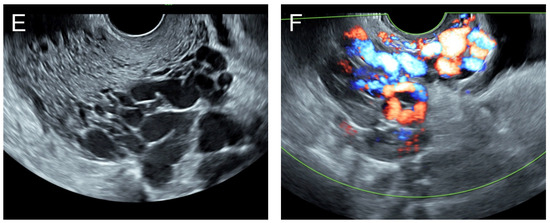

(A,B) Transvaginal ultrasound: sagittal scans of the uterus showed several small anechoic/hypoechoic cysts, giving a spongy pattern and varying in size, throughout the myometrium; no other specific lesions of the uterus. The uterine cavity was lined with a thin endometrium and filled with anechoic fluid, probably lysed blood. (C) Color flow mapping showed hyper-vascularization in the cystic spaces, as seen in figure (A,B), throughout the myometrium and a multidirectional chaotic flow. The main differential diagnosis was adenomyosis or gestational trophoblastic disease. (D) Spectral Doppler showed a high peak systolic velocity (~70 cm/s) with a low resistance index of 0.2.